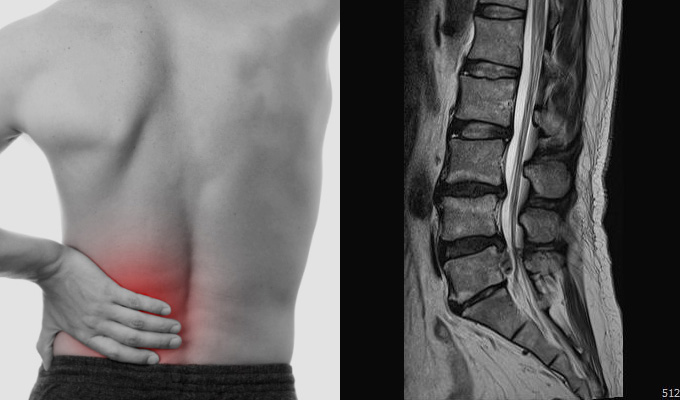

요즘은 허리디스크가

국민병이라고 불리고 있을 정도로

50~60대는 물론 10~30대 사이에도

흔히 생기고 있습니다.

특히 60대 이후로 발병률이 높아

노인성 질환으로 여겨져 왔던

'퇴행성 허리디스크' 역시 증가하고 있습니다.

허리디스크에 좋은 운동이 어떤것들이 있을까요?